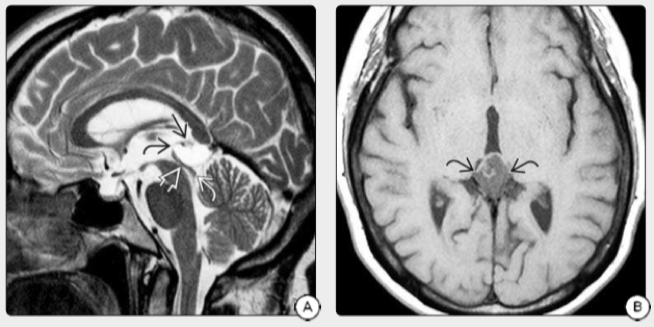

松果体区解剖复杂松果体呈近似圆形,附于三脑室顶部,中脑顶盖上方,肼胝体压部下方,其后方为大脑大静脉池,池内走行着收集大脑深组静脉血的大脑大静脉,此池向前上方通中间帆腔,向下连四叠体池。松果体瘤系指松果体肿瘤引起的促性腺激素及性激素分泌增多(松果体的分泌功能上与腺垂体有拮抗作用)又称性早熟综合征、早熟性巨生殖器巨体综合征。松果体区常见的肿瘤有:松果体细胞瘤、成胶质细胞瘤、畸胎瘤、生殖细胞瘤、精原细胞瘤、星形细胞瘤等。本文主要介绍松果体细胞瘤。

图1:松果体区的复杂解剖特点